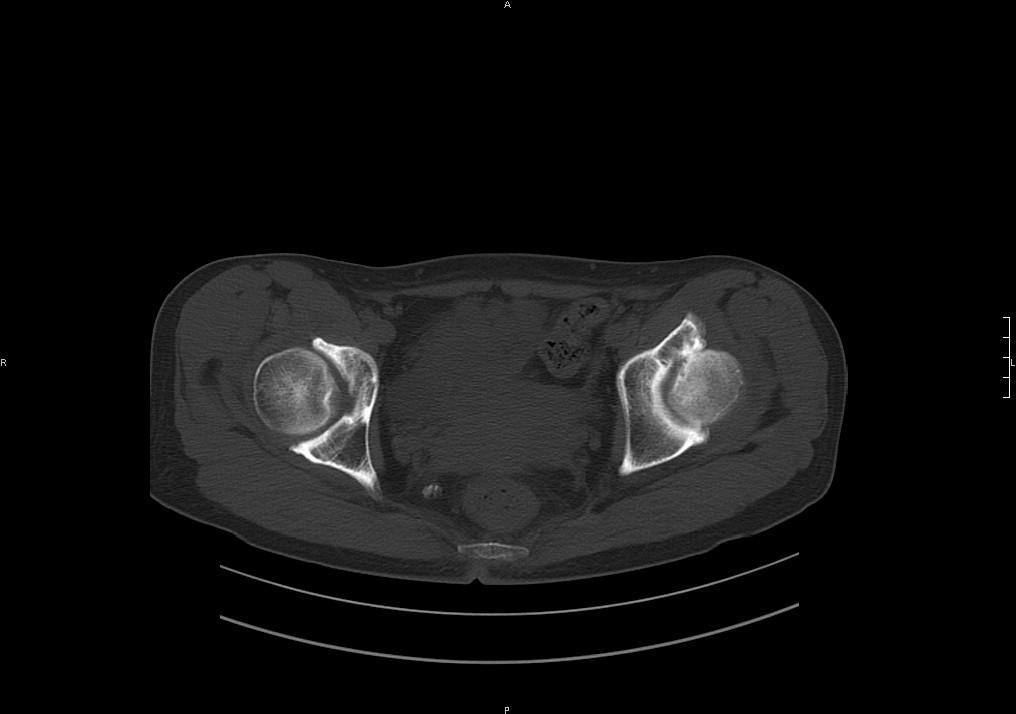

标题: CT19780左髋关节疼痛伴跛行1年,加重1个月。无菌性坏死? [打印本页]

标题: CT19780左髋关节疼痛伴跛行1年,加重1个月。无菌性坏死?

左髋关节内内可见关节鼠及滑囊积液.

考虑为滑膜骨软骨瘤病.

滑膜增厚钙化,关节鼠及滑囊积液,髋臼增生。考虑骨性关节病

髋臼平浅,股骨头覆盖率减小,考虑双侧髋关节发育不良伴退行性变。